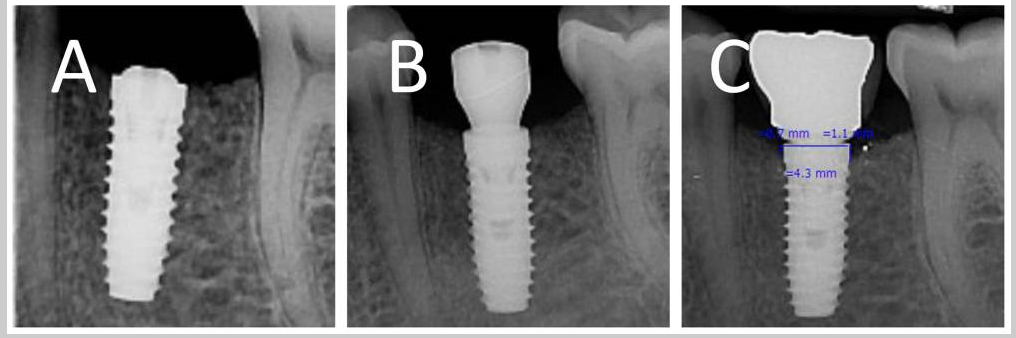

Case Study: Effect of vertical implant position on marginal bone loss

Case photos below provided by: Hedayatipanah M, Arasteh HK, Shokri A, Alafchi B, Baghdadi LS. Effect of vertical implant position on marginal bone loss: a randomized clinical trial.

Crestal implant: (A) baseline (B) three months after placement (C) three months after loading

Subcrestal implant: (A) baseline (B) three months after placement (C) three months after loading